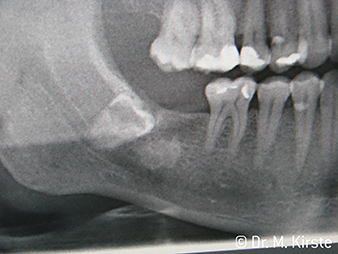

W&H X-Ray

Fig. 6:

Patient example: The displaced tooth 48 ...